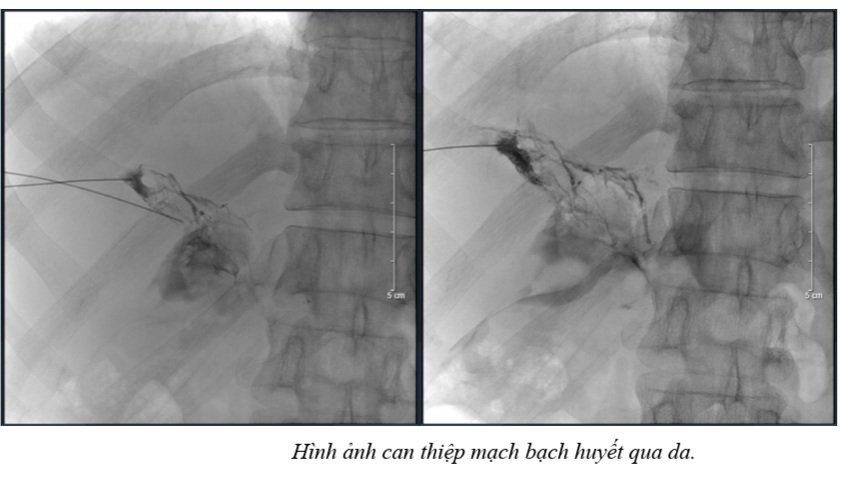

z3307918848565 070cb248eece5399786684b905a58f44Với đặc điểm kỹ thuật phức tạp, nên sau mổ, bệnh nhân có thể gặp một số vấn đề, một trong số đó là rò bạch huyết sau mổ. Đây là một biến chứng tương đối hiếm gặp tuy nhiên thường rất khó xử lý và ảnh hưởng không nhỏ đến chất lượng cuộc sống của bệnh nhân. Trong những trường hợp rò bạch huyết số lượng lớn không thể kiểm soát bằng việc điều chỉnh chế độ dinh dưỡng, nút mạch bạch huyết qua da (percutaneous hepatic lymphangiography) là phương pháp can thiệp tối thiểu đã cho thấy hiệu quả tốt, với nhiều ca bệnh được kiểm soát. Đây là một kỹ thuật can thiệp khó, chuyên sâu đã được thực hiện thành công tại Trung tâm Điện quang Can thiệp, Bệnh viện Bạch Mai. Kinh nghiệm điều trị rò bạch huyết đã được chúng tôi tổng kết và công bố bằng 2 bài báo đã được đăng tải trên các tạp chí Y khoa quốc tế.